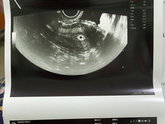

11 июля 2023 21:03 Добрый вечер девчули, с утра были адские боли в пояснице и низ живота болел…. Поехала в городскую больницу, на кресло не полезла сразу сказала…направила на повторное узи, по узи поставили срок 4-5 недель? прописали Дюфастон 2 р/д, эндометрий очень тонкий … Читать далее

11 июля 2023 07:11 Доброе утро девчули, пришел мой хгч? резкий рост. 26.06 был 28 а 28.06 был 38 теперь 322, буду сдавать в динамике следить ? главное чтоб развивался хорошо, а то узист говорит эндометрий 4мм главное чтоб удержался

10 июля 2023 12:45 У кого был эндометрий тонкий? Главное чтоб не было выкидыша, так как сказали он должен еще прикрепиться? срок 1-2 недели… хгч сдала тоже завтра будут готовы, сдавать в динамике отслеживать